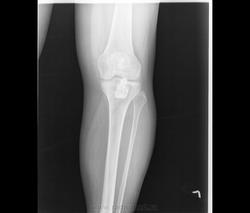

После рентгенографии и КТ направительный диагноз "костно-хрящевой экзостоз проксимального эпифиза, гиперостоз диафиза левой б/берцовой кости".

Коллеги, я же написала, что "остеохондрома (экзостоз)" был направительный диагноз, который сняли, проведя рентгеновское дообследование. Для экзостоза характерно: ножка исходит и имеет структуру губчатой кости, корковый слой переходит снаружи на ножку. Здесь образование исходит из коркового слоя (видно на КТ). Кроме того я указала, что в направительном диагноза (видно в нижних отделах бокового снимка) есть гиперостоз диафиза б/берцовой кости.

Обратите внимание, помимо гиперостоза, в дистальном эпифизе б/берцовой кости, 1 плюсневой кости и проксимальной фаланге 1 пальца - внутрикостные очаги склероза. Т.о.: гиперостоз, остеосклероз и гететопические оссификаты костей левой нижней конечности.

Микроскопическая картина: фрагменты костных балок с явлениями гиперостоза, утолщенные элементы ламеллярной кости на отдельных участках с резким сужением и облитерацией гаверсовых каналов, очаговый межбалочный фиброз с замещением элементов жирового костного мозга.